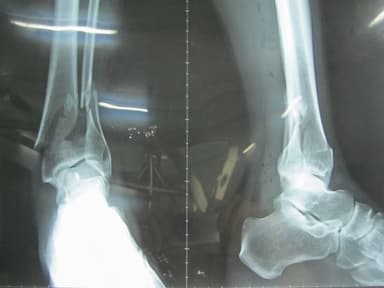

Thông thường gãy xương mác mà không can thiệp phẫu thuật tức là chỉ cố định xương bằng nẹp rồi bó bột lại thì quá trình lành xương từ 1-2 tháng trở lên. Tuy nhiên, để xương trở về cấu trúc ban đầu cần mất nhiều thời gian hơn và phụ thuộc vào nhiều yếu tố khác như tuổi tác, chế độ dinh dưỡng, sinh hoạt, vận động sau gãy.

Để có thể đứng lên đi lại được chồng bạn cần khoảng thời gian 5-6 tuần. Lúc này, chồng bạn nên dùng nạng gỗ tập đi.